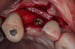

Following a GBR at the time of implant placement (Pictures 1,2,3), a buccal ridge deficiency persisted (Picture 4). Surgical uncovery of the implant to expose the cover screw revealed successful bone regeneration around the implant, but a residual lack of ridge contour (Picture 5).

Instead of using a traditional particulate graft covered with a resorbable membrane, a “flexible bone graft” sheet, DALI Flex Graft, was placed over the buccal plate to augment the buccal contour (Pictures 6 & 7). Because the graft comes hydrated, it is easy to handle and adapt to the defect location. The flap was then pulled over the graft and adapted around the healing abutment (Picture 8).